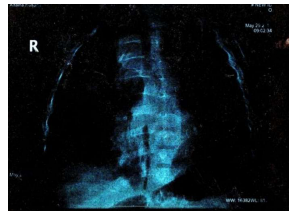

recessions, with respiratory rate of 30 breaths per minute. He had aloud respiratory grunt. The chest expansion was reduced which was dull on percussion. Asculation revealed a marked reduction of air entry over the mid and upper zones. Chest-X ray showed a well demarcated opacity involving the upper and mid zones. Ultrasound scan of the chest revealed fluid-filled right costophrenic angle, suggesting a pleural effusion.

A contrast-enhanced Computer Tomography Scan of the chest showed: a large mass filling the posterior mediastinum in it's upper and middle parts, aligned with the visceral side of the right upper lobe.